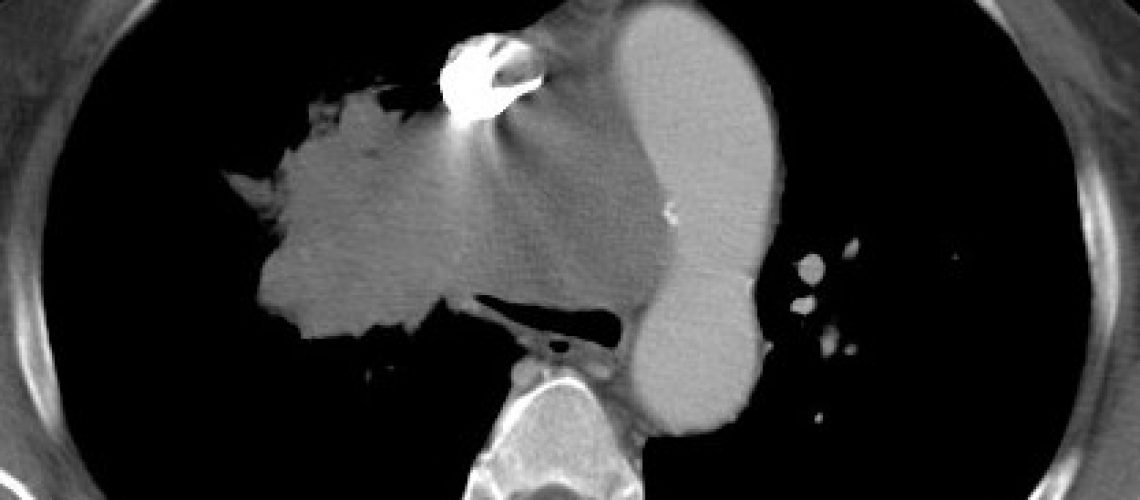

Es uno de los cánceres mas agresivos y mas frecuentes en hombres y mujeres.  En el 90% de los casos ocurre en fumadores de larga evolución. Existen diferentes tipos de tumores que se tratan de forma diferente según el tipo de células que predominan en la lesión. Los síntomas de alerta que deben llevar a solicitar atención médica son la tos persistente, la expectoración de sangre con la mucosidad, la pérdida injustificada de peso o el dolor torácico. Es de vital importancia el diagnóstico precoz pues el cáncer de pulmón es curable en estadios iniciales pero el pronóstico empeora mucho en estadios avanzados.